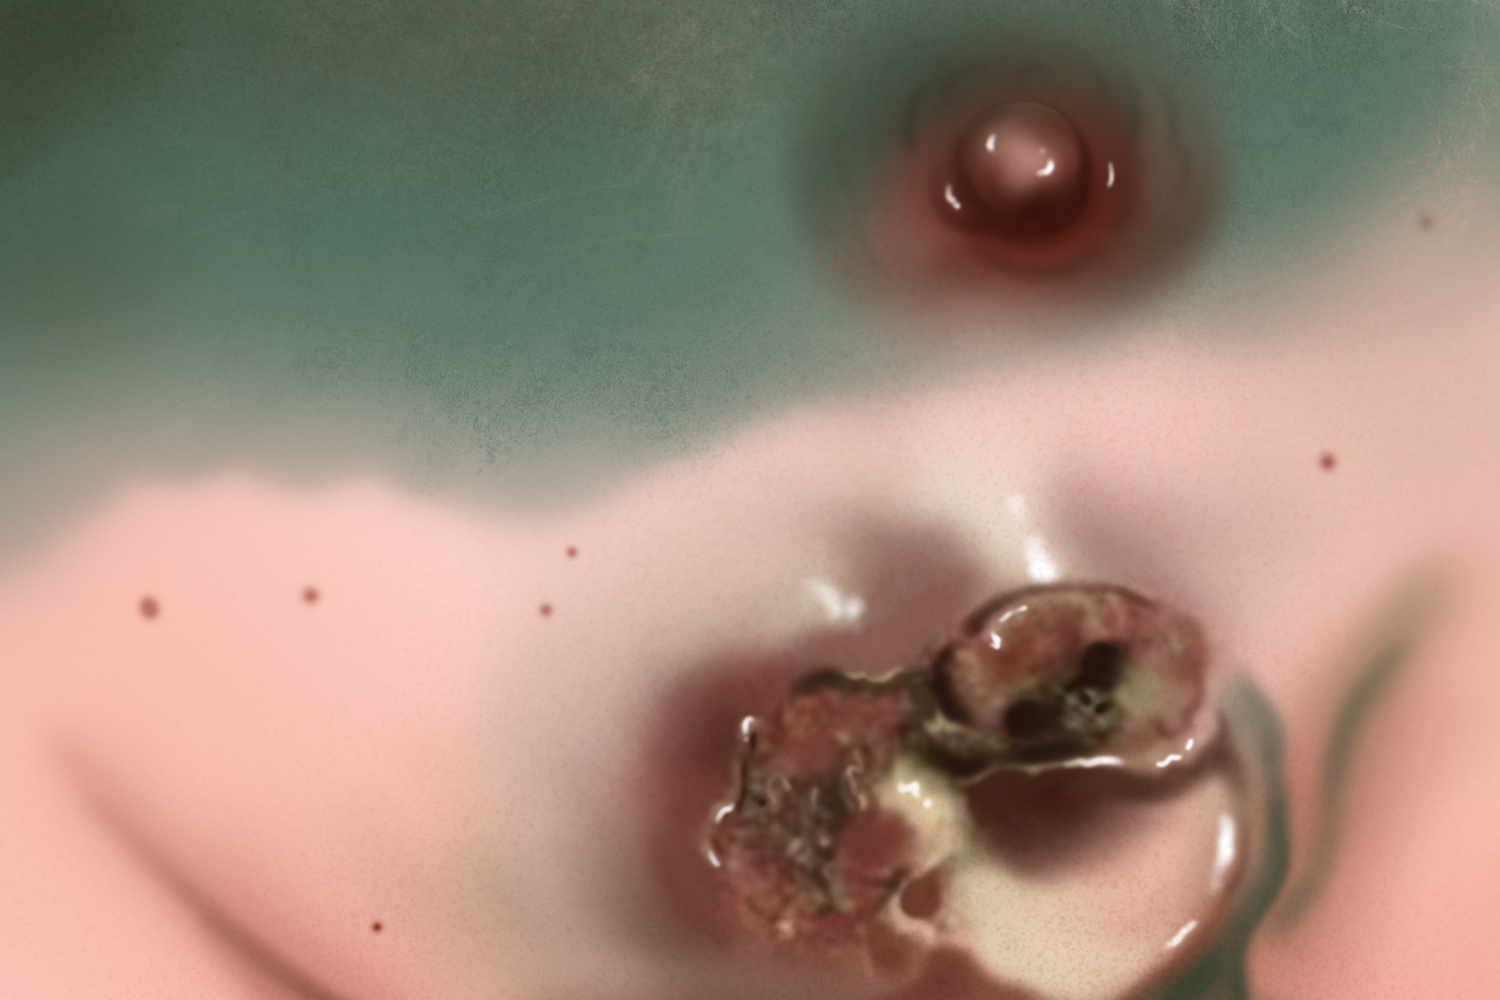

乳头乳晕湿疹样癌:是乳腺癌的特殊类型,主要表现为乳头乳晕皮肤发红和湿疹样改变,乳头瘙痒、烧灼感或刺痛。反复发作后局部皮肤增厚、渗出、溃烂和结痂,乳头内陷、溃烂,甚至出现整个乳头坏死。

乳头乳晕湿疹样癌:主要病因与遗传因素、生育因素、乳腺疾病史、月经史等有关,以上因素可导致乳腺癌的发生,又因癌细胞的浸润即可导致乳房组织的改变,从而可发生局部感染、溃烂。